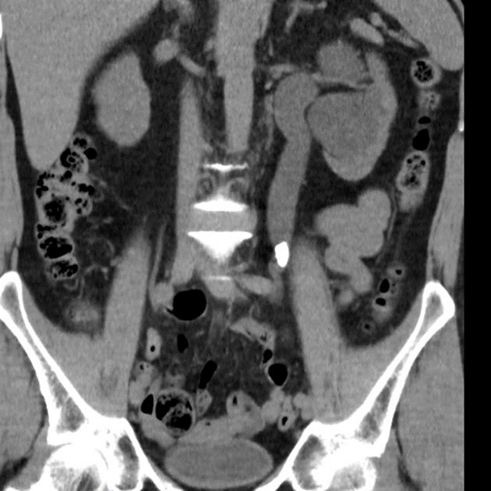

Vad ses på bilden?

Samlingssystemet med uttalad hydronefros, uttalad hydrouretär ned till konkrement i övergång mellan proximal uretär och mellersta delen ureätär

DT visar

• Samlingssystemet med uttalad hydronefros, uttalad hydrouretär ned till konkrement i övergång mellan proximal uretär och mellersta delen ureätär